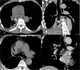

Bronchial wall thickening